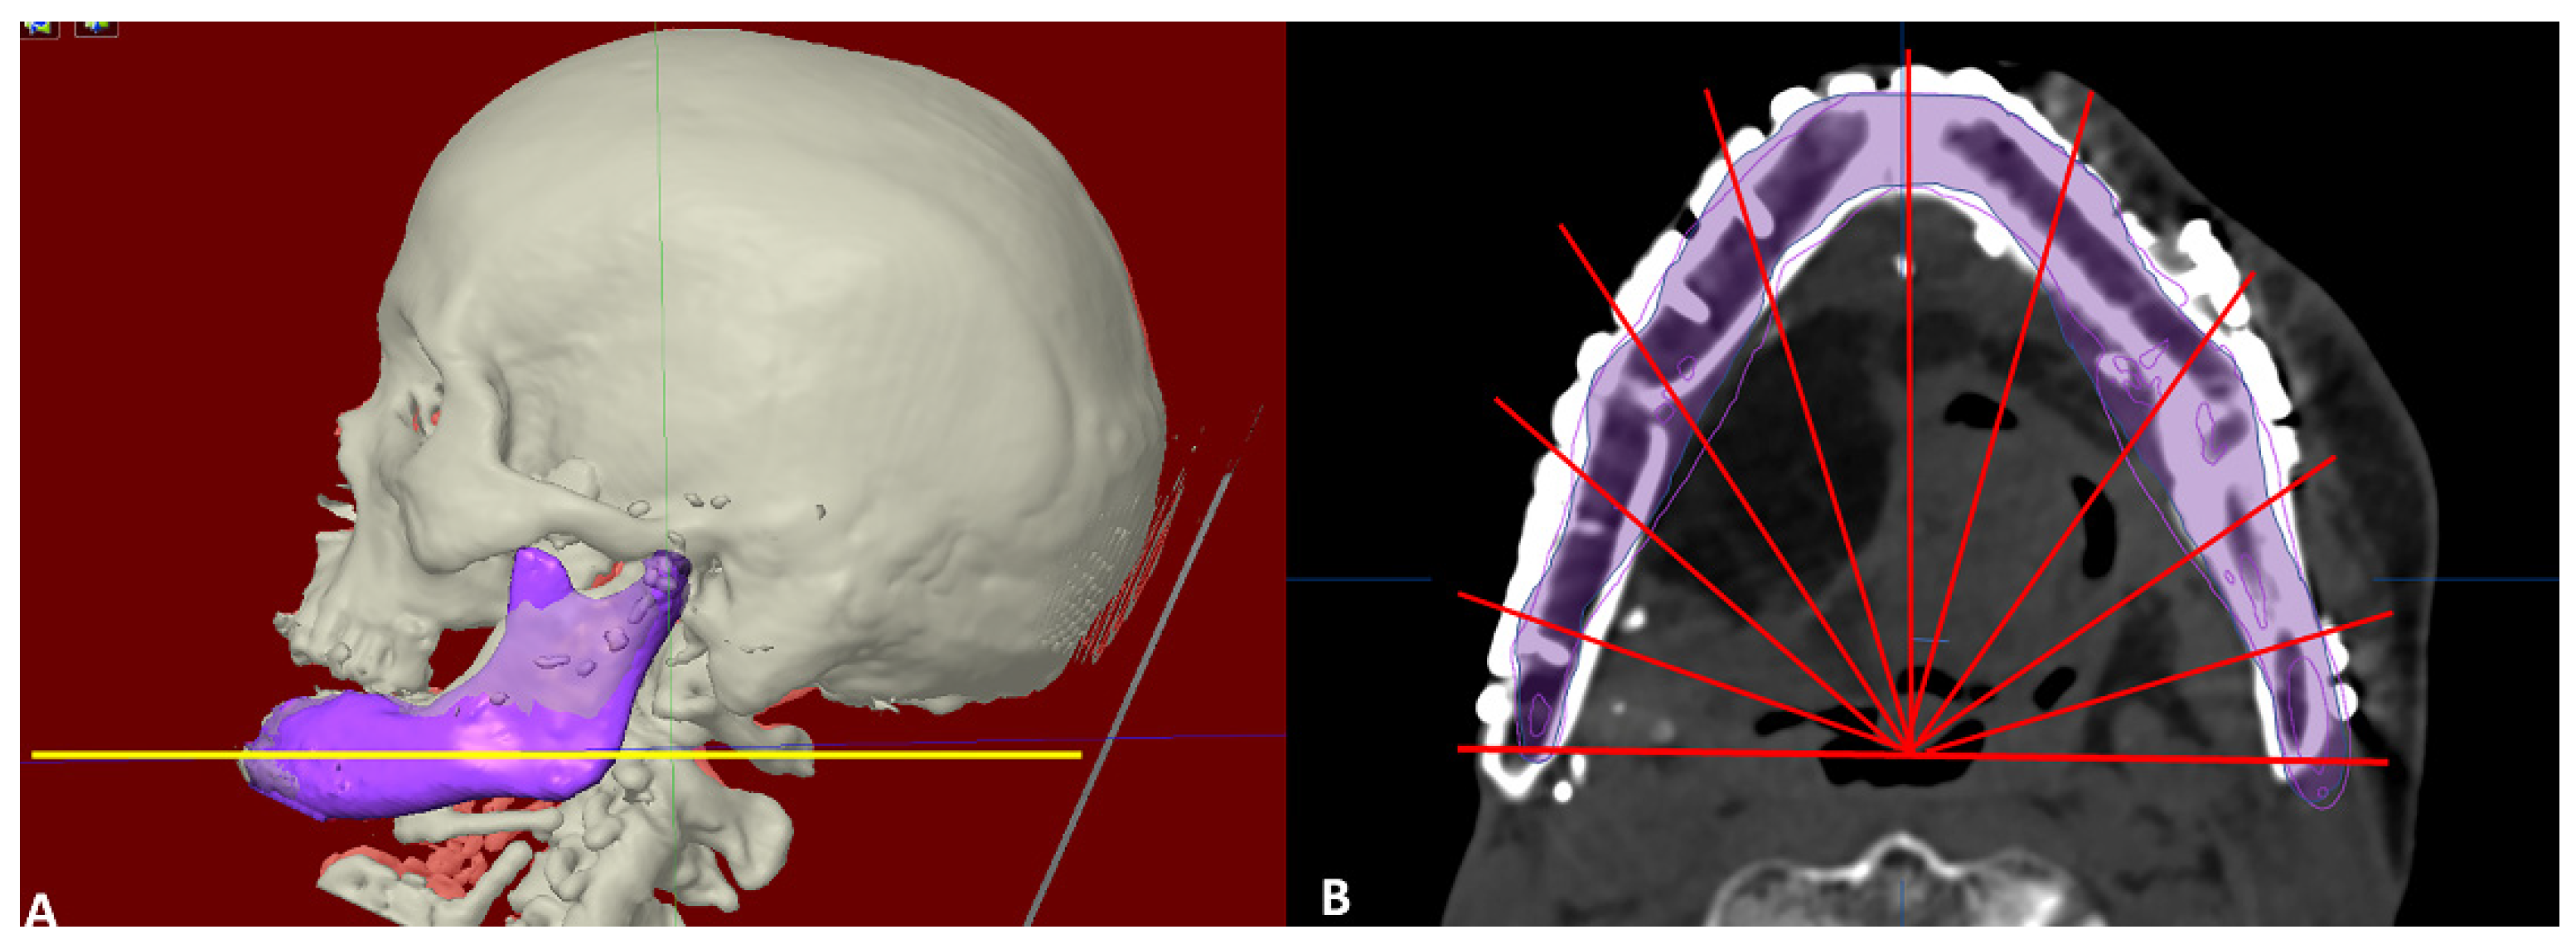

Designing template in category I. (A) 3-dimensional view of defect. (B) Segmentation of right hemimandible (blue color). (C) Mirroring to the left side (pink color). (D) Merging both sides to form simulated whole mandible for printing (yellow color).

Category I included the cases where the reconstruction defect did not cross the midline. ‘Mirroring’ function integrated in the software was used to obtain the template of the defect from the normal sided mandible and whole mandible could be virtually constructed. Since the position of residual mandible is distorted in most of cases of secondary reconstructions, the residual mandible was also realigned to near-original position, taking occlusal relation as a guide and then mirroring it (Figure 2).

Figure 2.